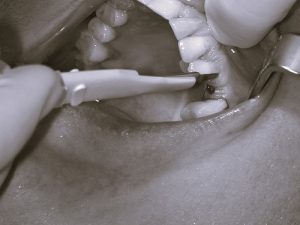

Anstatt das Zahnfleisch weiträumig aufzuschneiden, wird lediglich mit einer kleinen Stanze etwas Zahnfleisch abgetragen und anschließend ein Loch in den Knochen gebohrt.

Schließlich wird das passende Implantat eingebracht, womit automatisch das Stanzloch verschlossen und folglich eine offene Operationswunde komplett vermieden wird.

Die Operation dauert pro Implantat selten länger als 10 bis 15 Minuten und durch das Wegfallen einer offenen Operationswunde sind auch keine Nähte erforderlich und Schmerzen oder Schwellungen treten nur in den seltensten Fällen auf.